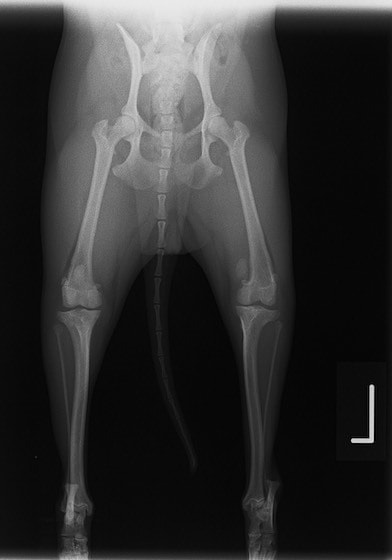

■ 症例22 ポメラニアン 1歳5か月 去勢雄

左後肢の挙上を主訴に来院した。整形学的検査、レントゲン検査より左右の膝蓋骨脱臼(左GradeⅡ〜Ⅲ、右Grade Ⅱ)を認めた。また、脛骨の前方引き出し試験の際に、引き出し兆候は認められないものの、疼痛が認められたため、前十字靭帯の損傷が疑われた。術中における、目視および関節内の操作によって、前十字靭帯の損傷や過伸展といった異常が認められなかったため、膝蓋骨脱臼の整復のみ実施した。手術手技は縫工筋及び内側広筋の解放、脛骨粗面の外側転位、滑車ブロック形造溝術、内外側関節包の縫縮を実施した。本症例は跛行もなく経過良好である。しかし、頸骨高平部の角度(TPA)が 右26.2°、左24.9°であり、解剖学的に前十字靭帯損傷のリスクが高いことから今後の経過に注意が必要である。